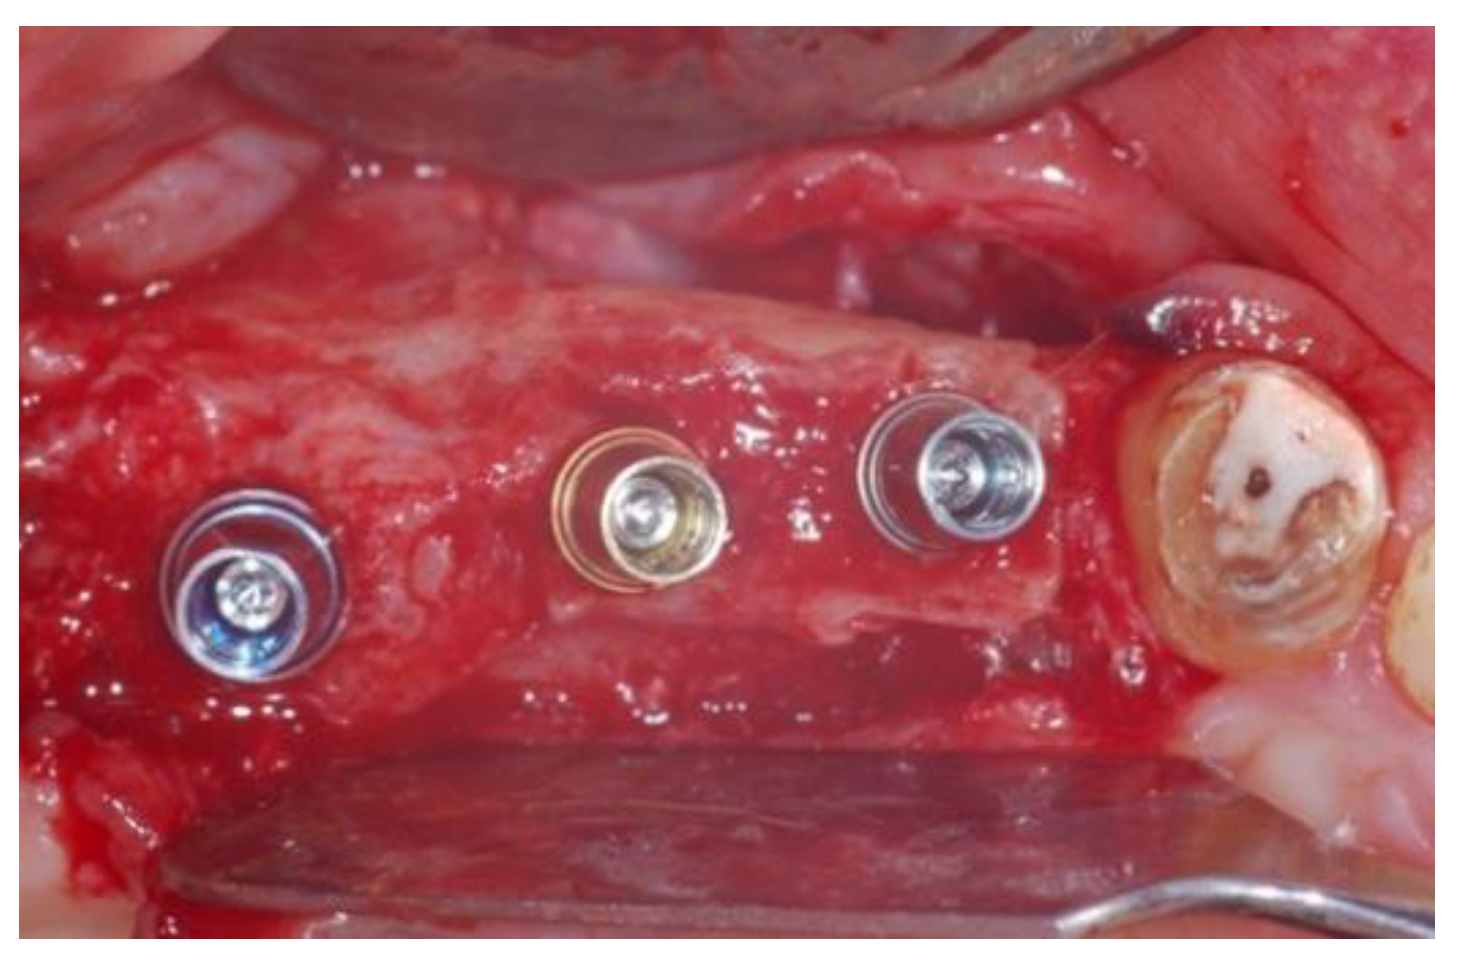

2.1. Surgical Procedures